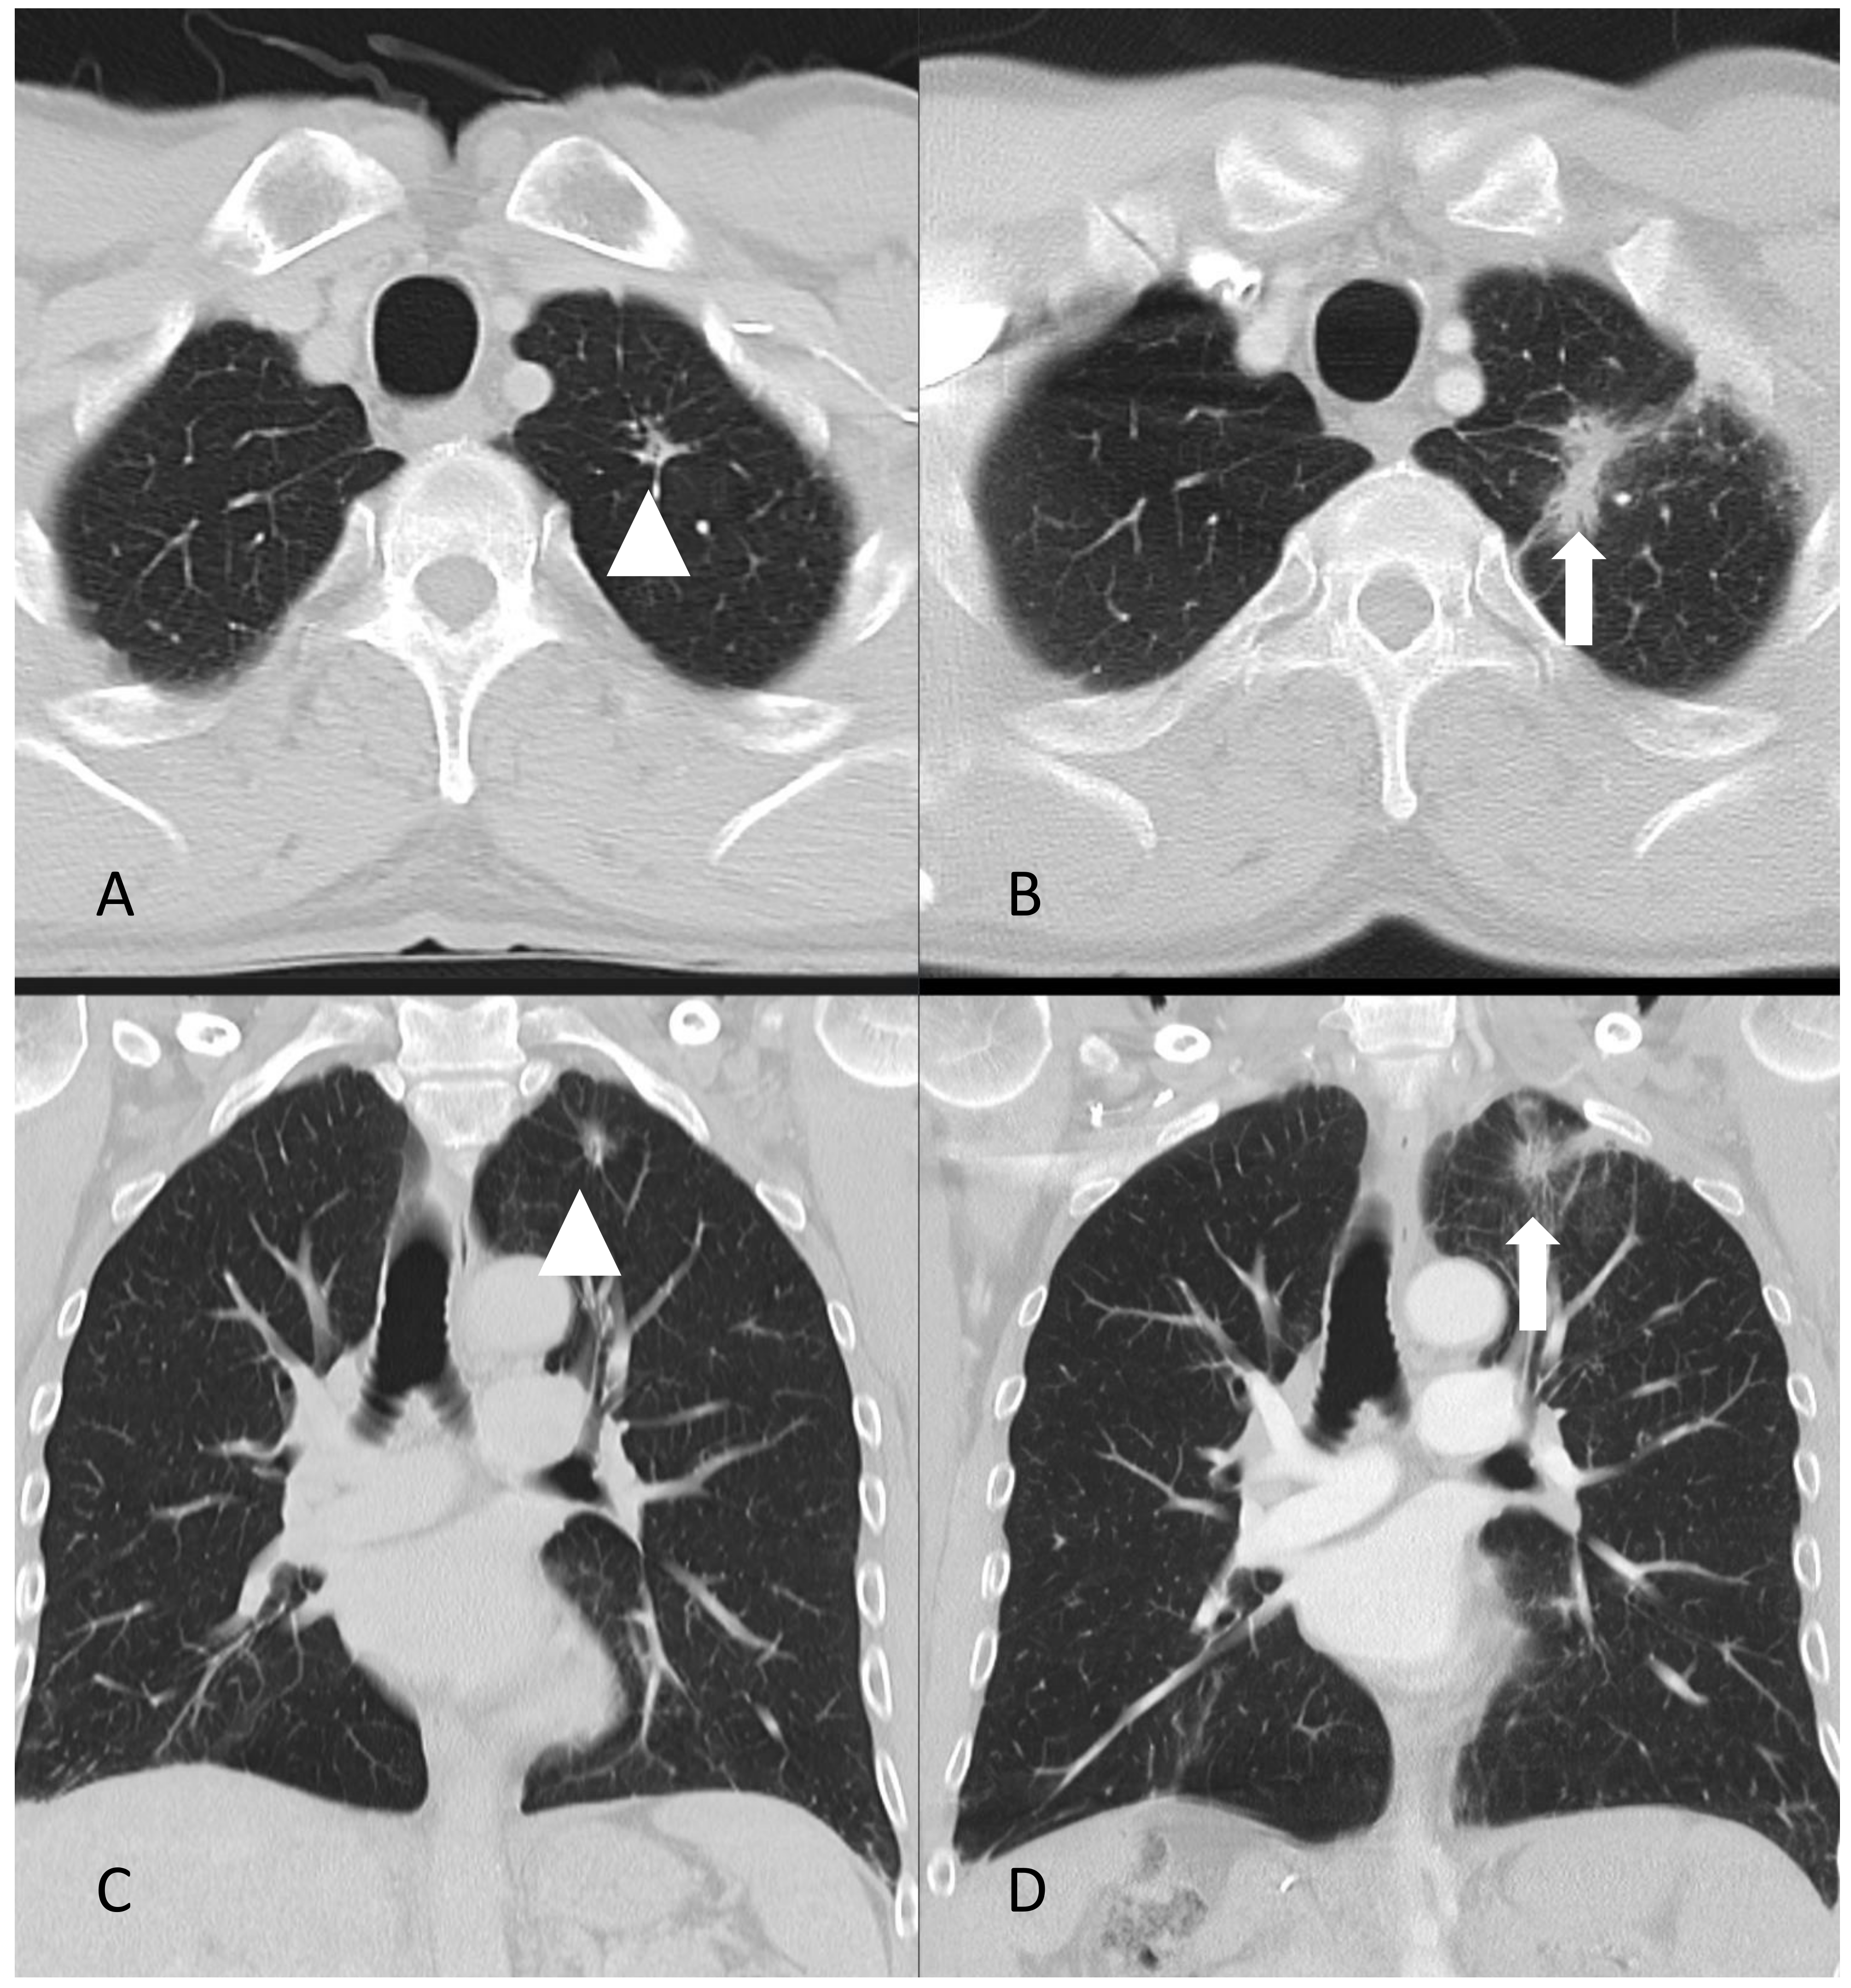

- A case of a patient with AIP type 1 and other organ involvement (bile ducts, testicles, nasal polyps, and lungs) is described.